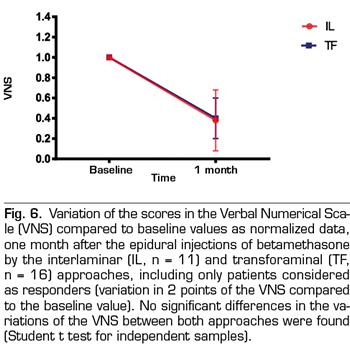

When the changes in the VNS and the Interference Score of those patients whose responses were considered positive using betamethasone interlaminar or transforaminal (11 and 16, respectively) were compared, no differences were found for any of these parameters (Figures 6 and 7).

The score in the VNS of the patients treated with betamethasone by interlaminar route changed from 8.4 ± 1.4 to 3.2 ± 3, which is equivalent to 61 % of improvement, whereas the Interference Score hanged from 6.5 ± 2.2 to 4.5 ± 2, which is equivalent to 30 % of improvement. In the case of betamethasone administered by transforaminal route, the VNS went from of 8.7 ± 1.1 to 3.3 ± 2.3, which is equivalent to 63 % of improvement, whereas the Interference Score decreased from 7.13 ± 2.1 to 4.75 ± 3.1, which is equivalent to 33 % of improvement.

Figure 6 shows the changes observed in the intensity of pain in the patients who showed positive responses in both groups, expressed as percentage of change. In both groups patients pain changed from intense to mild pain. Therefore, considering separately the group from “responders”, pain went from high to mild intensity in both groups, with an improvement of 2 points in terms of the functional impact of pain measured with the Interference Score (Figure 7). No statistically significant differences in the results were found comparing both approaches when the patients with positive responses were considered separately.